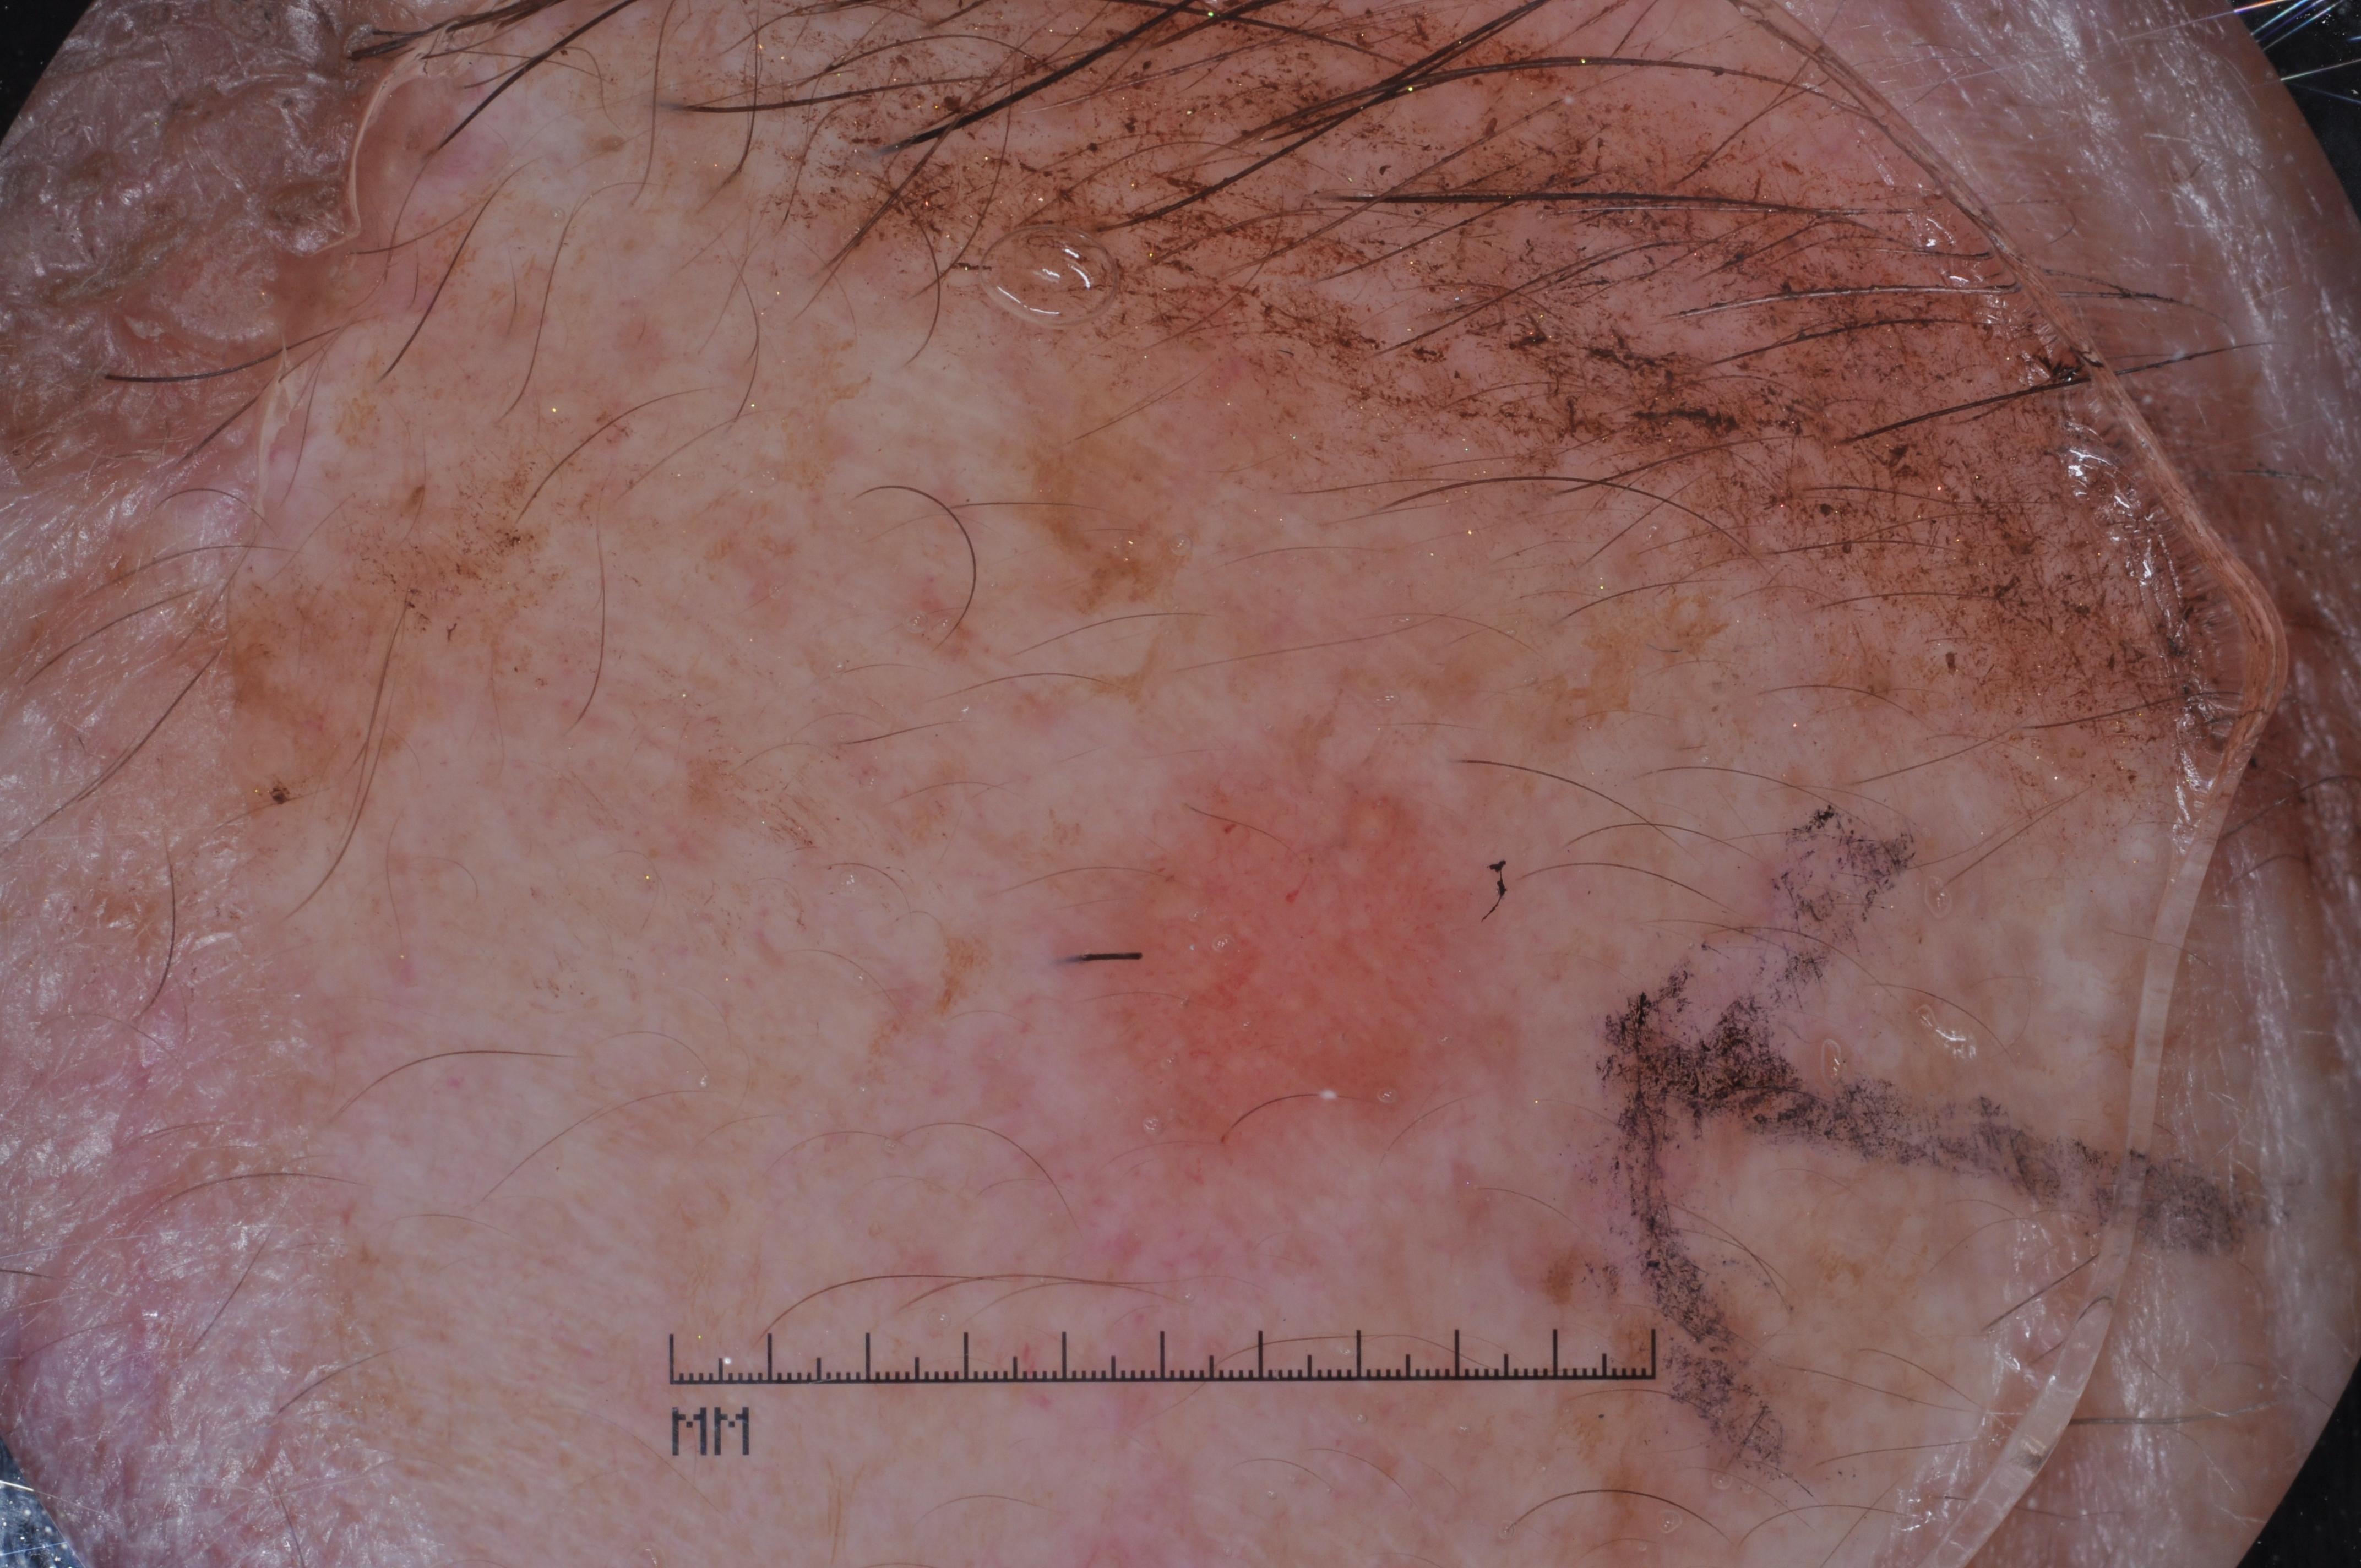

{

"age_approx": 60,

"anatom_site_general": "lower extremity",

"concomitant_biopsy": true,

"dermoscopic_type": "contact non-polarized",

"diagnosis_1": "Indeterminate",

"diagnosis_2": "Indeterminate melanocytic proliferations",

"diagnosis_3": "Atypical intraepithelial melanocytic proliferation",

"diagnosis_confirm_type": "histopathology",

"image_type": "dermoscopic",

"lesion_id": "IL_6551915",

"melanocytic": true,

"sex": "female"